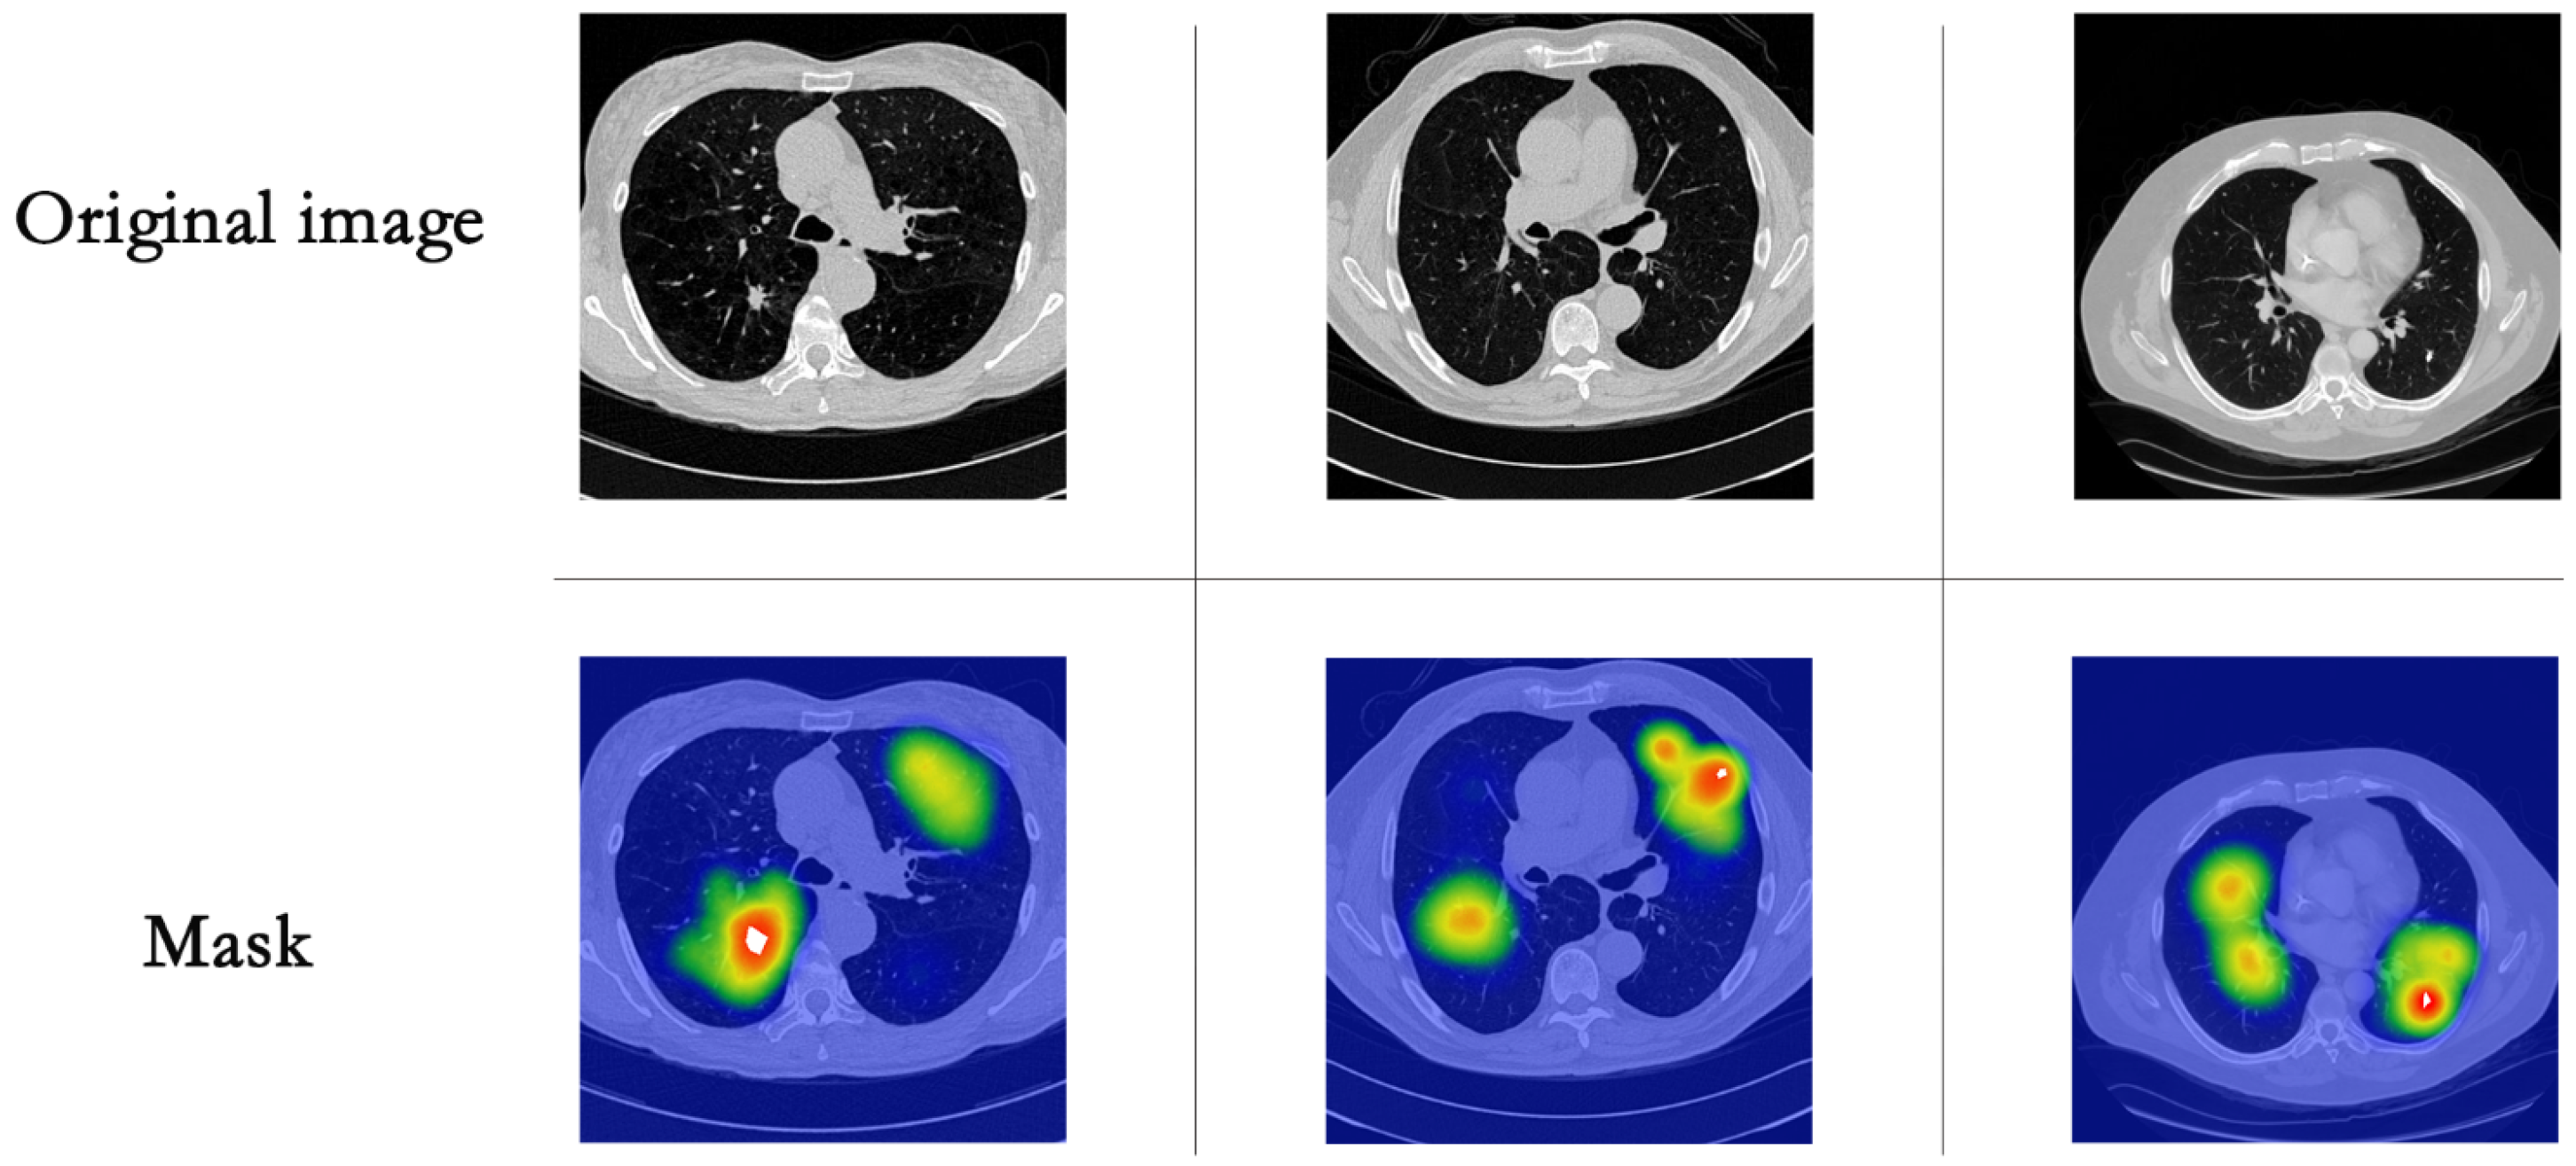

4.1. Data and Pre-Processing of Data